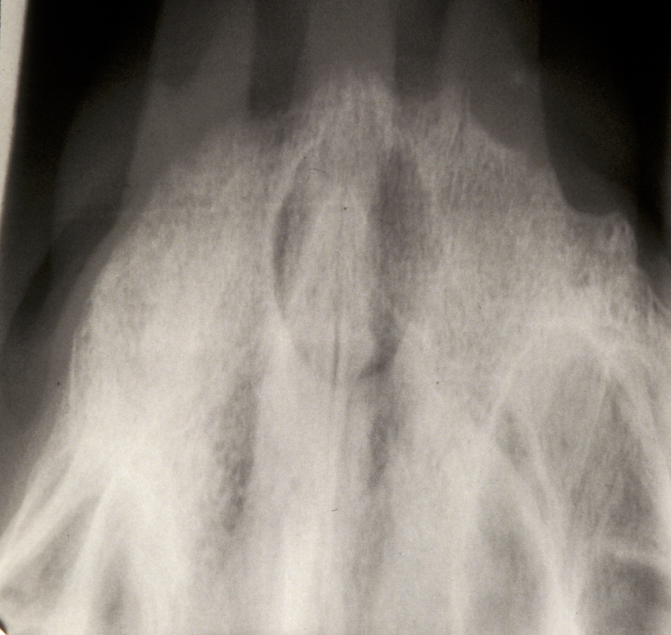

Thyroglossal duct cysts most frequently present in young children, although the age range is wide. The majority of these cysts lie in the midline of the neck (90%). These are mostly painless central neck masses which move on swallowing and elevate on protruding the tongue (see Figure 7).